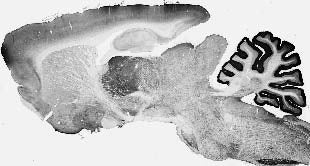

| 31859031 | 1:150 | Stoyas, C.A., et al. 2020. Nicotinamide Pathway-Dependent Sirt1 Activation Restores Calcium Homeostasis to Achieve Neuroprotection in Spinocerebellar Ataxia Type 7. Neuron, 630-644. |